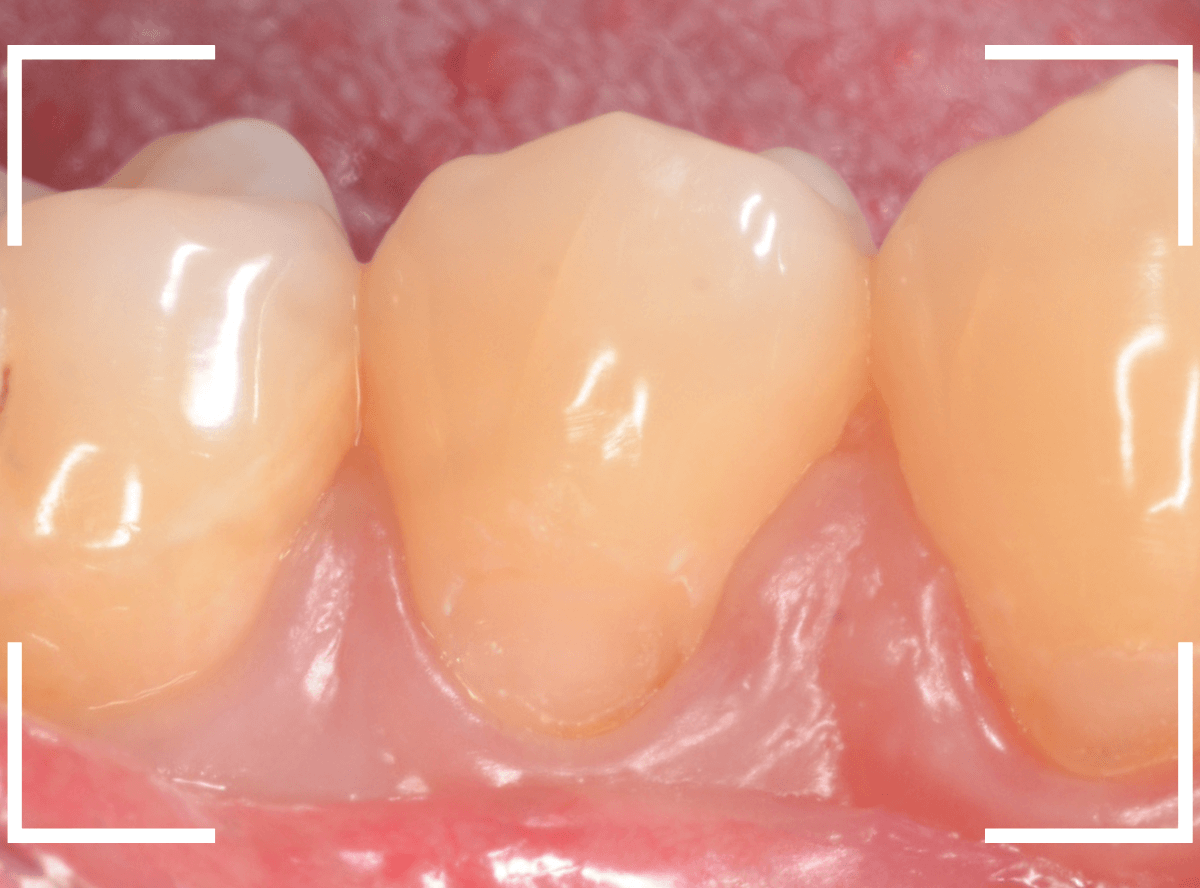

Case.1

時々、下の奥歯がしみるという症状で、久しぶりに来院された患者さんです。

風を当てる機械でしみる場所を探ってみると、歯の付け根あたりでとても反応がありました。

典型的な知覚過敏といっていいでしょう。

先ほどの画像ではよくわかりづらかったですが、しみる部分を上から見てみると、少し凹んでるのがわかりますでしょうか。

これは、過度な歯ブラシや歯ぎしりなどが原因で歯の側面が摩耗している状態です。

何も感じない方も多く、その場合はあえて何もしない事も多いのですが、今回のように、大きな知覚過敏症状が出てしまう事もあります。

今回のように目に見えて凹んでる部分が見られる場合は、対処が簡単な事が多いです。

こちらの写真でもわかりづらいですが、摩耗した部分に、レジンを少し盛ってあげる。

これだけで、劇的に症状が治まる事がほとんどです。

今回も、症状は劇的に緩和されました。

ただし、過度な歯ブラシや歯ぎしりが続く場合、レジンも短期間で外れてしまう事も多いですので、歯ブラシの仕方を変えたり、歯ぎしり防止のマウスピースを作るなどの対処も一緒に考える必要があります。